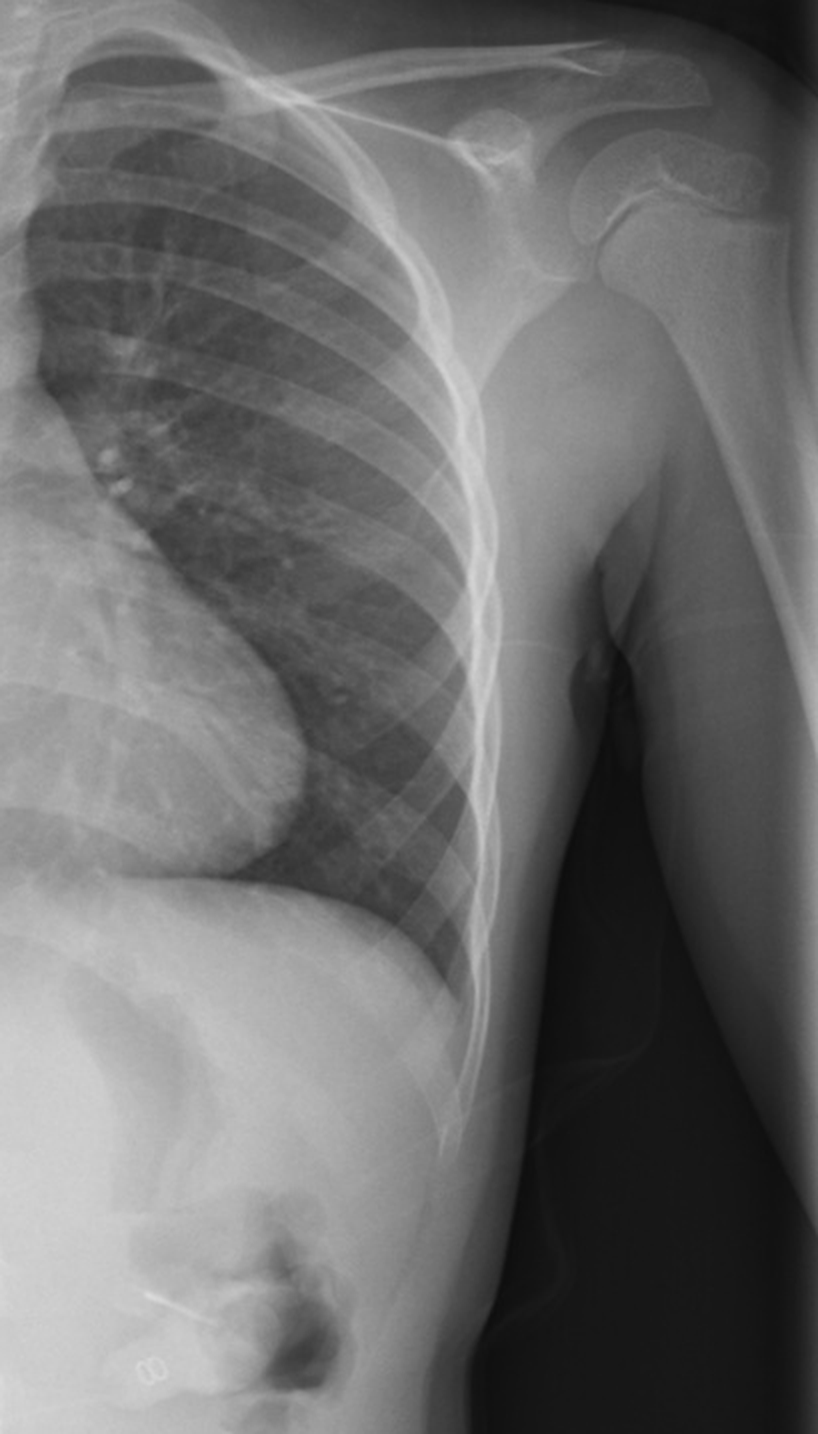

Refer to caption

Figure 1: Overview of MedVistaGym, which contains a comprehensive suite of reasoning-intensive medical image analysis tasks and tools in an interactive execution environment, scaling visual-centric tool-integrated agentic reinforcement learning for VLM agents.